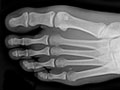

Extremity X-Ray

Test Overview An extremity

X-ray is a picture of your hand, wrist, arm, foot,

ankle, knee, hip, or leg. It is done to see whether a bone has been

fractured or a joint

dislocated. It is also used to check for an injury or

damage from conditions such as an infection,

arthritis, bone growths (tumors), or other bone

diseases, such as

Vancouver) or 10 days in the Rocky Mountains (Denver, Colorado). ResultsAn extremity X-ray is a picture of your

hand, wrist, arm, foot, ankle, knee, or leg. It is done to see whether your

bone has been

fractured or your joint

damage from conditions such as infection,

osteoporosis. In an emergency, the doctor can see the